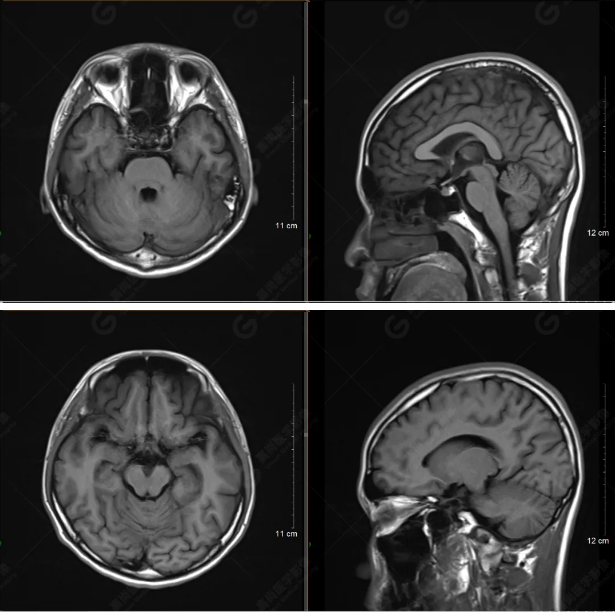

以下是T1WI軸位掃描及矢狀位掃描:

雙側(cè)大腦半球?qū)ΨQ,灰白質(zhì)對比正常,顱內(nèi)未見異常信號影。腦室系統(tǒng)未見擴(kuò)大,中線結(jié)構(gòu)居中。腦溝、裂未見增寬。幕下小腦、腦干未見異常。矢狀位示垂體形態(tài)、大小級信號未見異常。所示左側(cè)乳突內(nèi)見多發(fā)短T1長T2信號影。

顱腦MRI平掃未見明顯異常,左側(cè)乳突內(nèi)積血,建議補(bǔ)充SWI檢查。(左側(cè)為薄層原始圖像,右側(cè)為后處理5mm圖像)